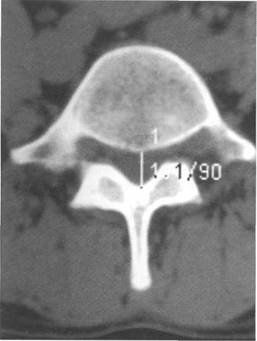

К моменту рождения (рис. 3.1) тело позвонка почти полностью состоит из к 141s183b 86;стной ткани, за исключением лимбусов, которые остаются хрящевыми. Дуга представлена двумя половинами, не слившимися ни с телом позвонка, ни между собой. Суставные отростки сохраняют перифе

Ti

(lamina)

(uncus)